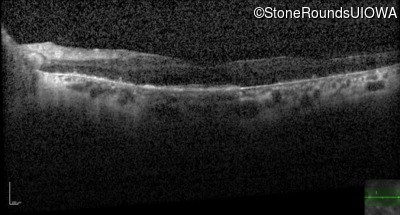

Optical Coherence Tomography - Right - 20/25

Exemplar / OCT Stack